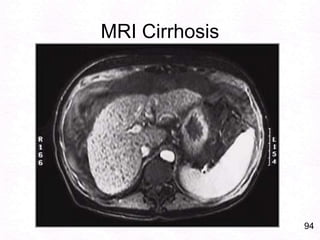

94MRI Cirrhosis